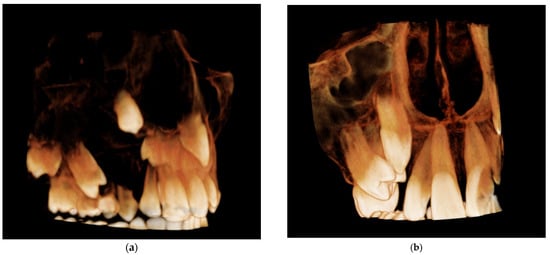

An interdisciplinary treatment plan was established to achieve the best therapeutic result and reduce the risk of complications. The first surgical step included a minimally invasive approach, and marsupialization was the method of choice. After the procedure, an alginate impression was taken, and an acrylic obturator was made. The aim was to maintain communication between the cyst and the oral cavity and reduce intracystic pressure. This helped to prevent the accumulation of debris in the post-surgery area and the formation of a fibrous scar that could be an obstacle to the eruption of teeth. A follow-up with radiological assessment was performed 2, 4 and 6 months after marsupialization. The size of the lesion decreased rapidly, and the unerupted 13 gradually migrated into a more promising position (Figure 7, Figure 8, Figure 9, Figure 10 and Figure 11). After 6 months, a second surgery was performed to remove the whole lesion. Bone scrapings were sent for histopathological verification. The examination confirmed a cyst composed of loose connective tissue. The epithelial lining was thin and acantholytic.

Figure 11.

Comparison of three-dimensional CBCT reconstruction before surgery (a) and 6 months after surgery (b).

In the presented case, the prompt eruption of Tooth 13 after marsupialization was possible due to the existence of promising factors, as described above and highlighted in Figure 15. The apex was open, and the root (R) did not achieve 2/3 of its final length. Because the adjacent teeth were malpositioned, as a reference line to assess angulation (A), the midline was chosen (as an analogy to Ericson and Kurol’s classification) [38]. The low value of the angle and almost-parallel position of the canine germ according to the midline gave a reasonable assumption that a spontaneous eruption was possible. The cusp depth (D) is appropriate to the stage of development because, according to Coulter et al. [39], the predominant vertical eruption path can be still expected. The upper right premolars revealed a less favorable position, inclined more horizontally. CBCT confirmed vesibuloposition with a poor alveolar boundary condition that required careful application of orthodontic force to achieve their proper alignment.